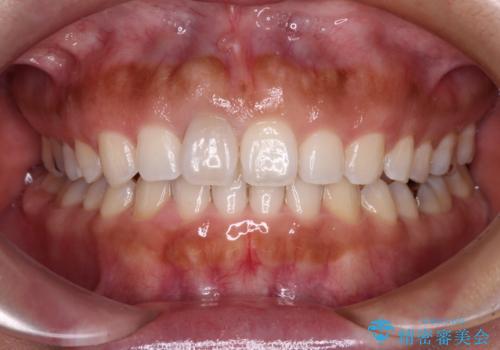

前歯のがたつき 深い噛み合わせを改善したい